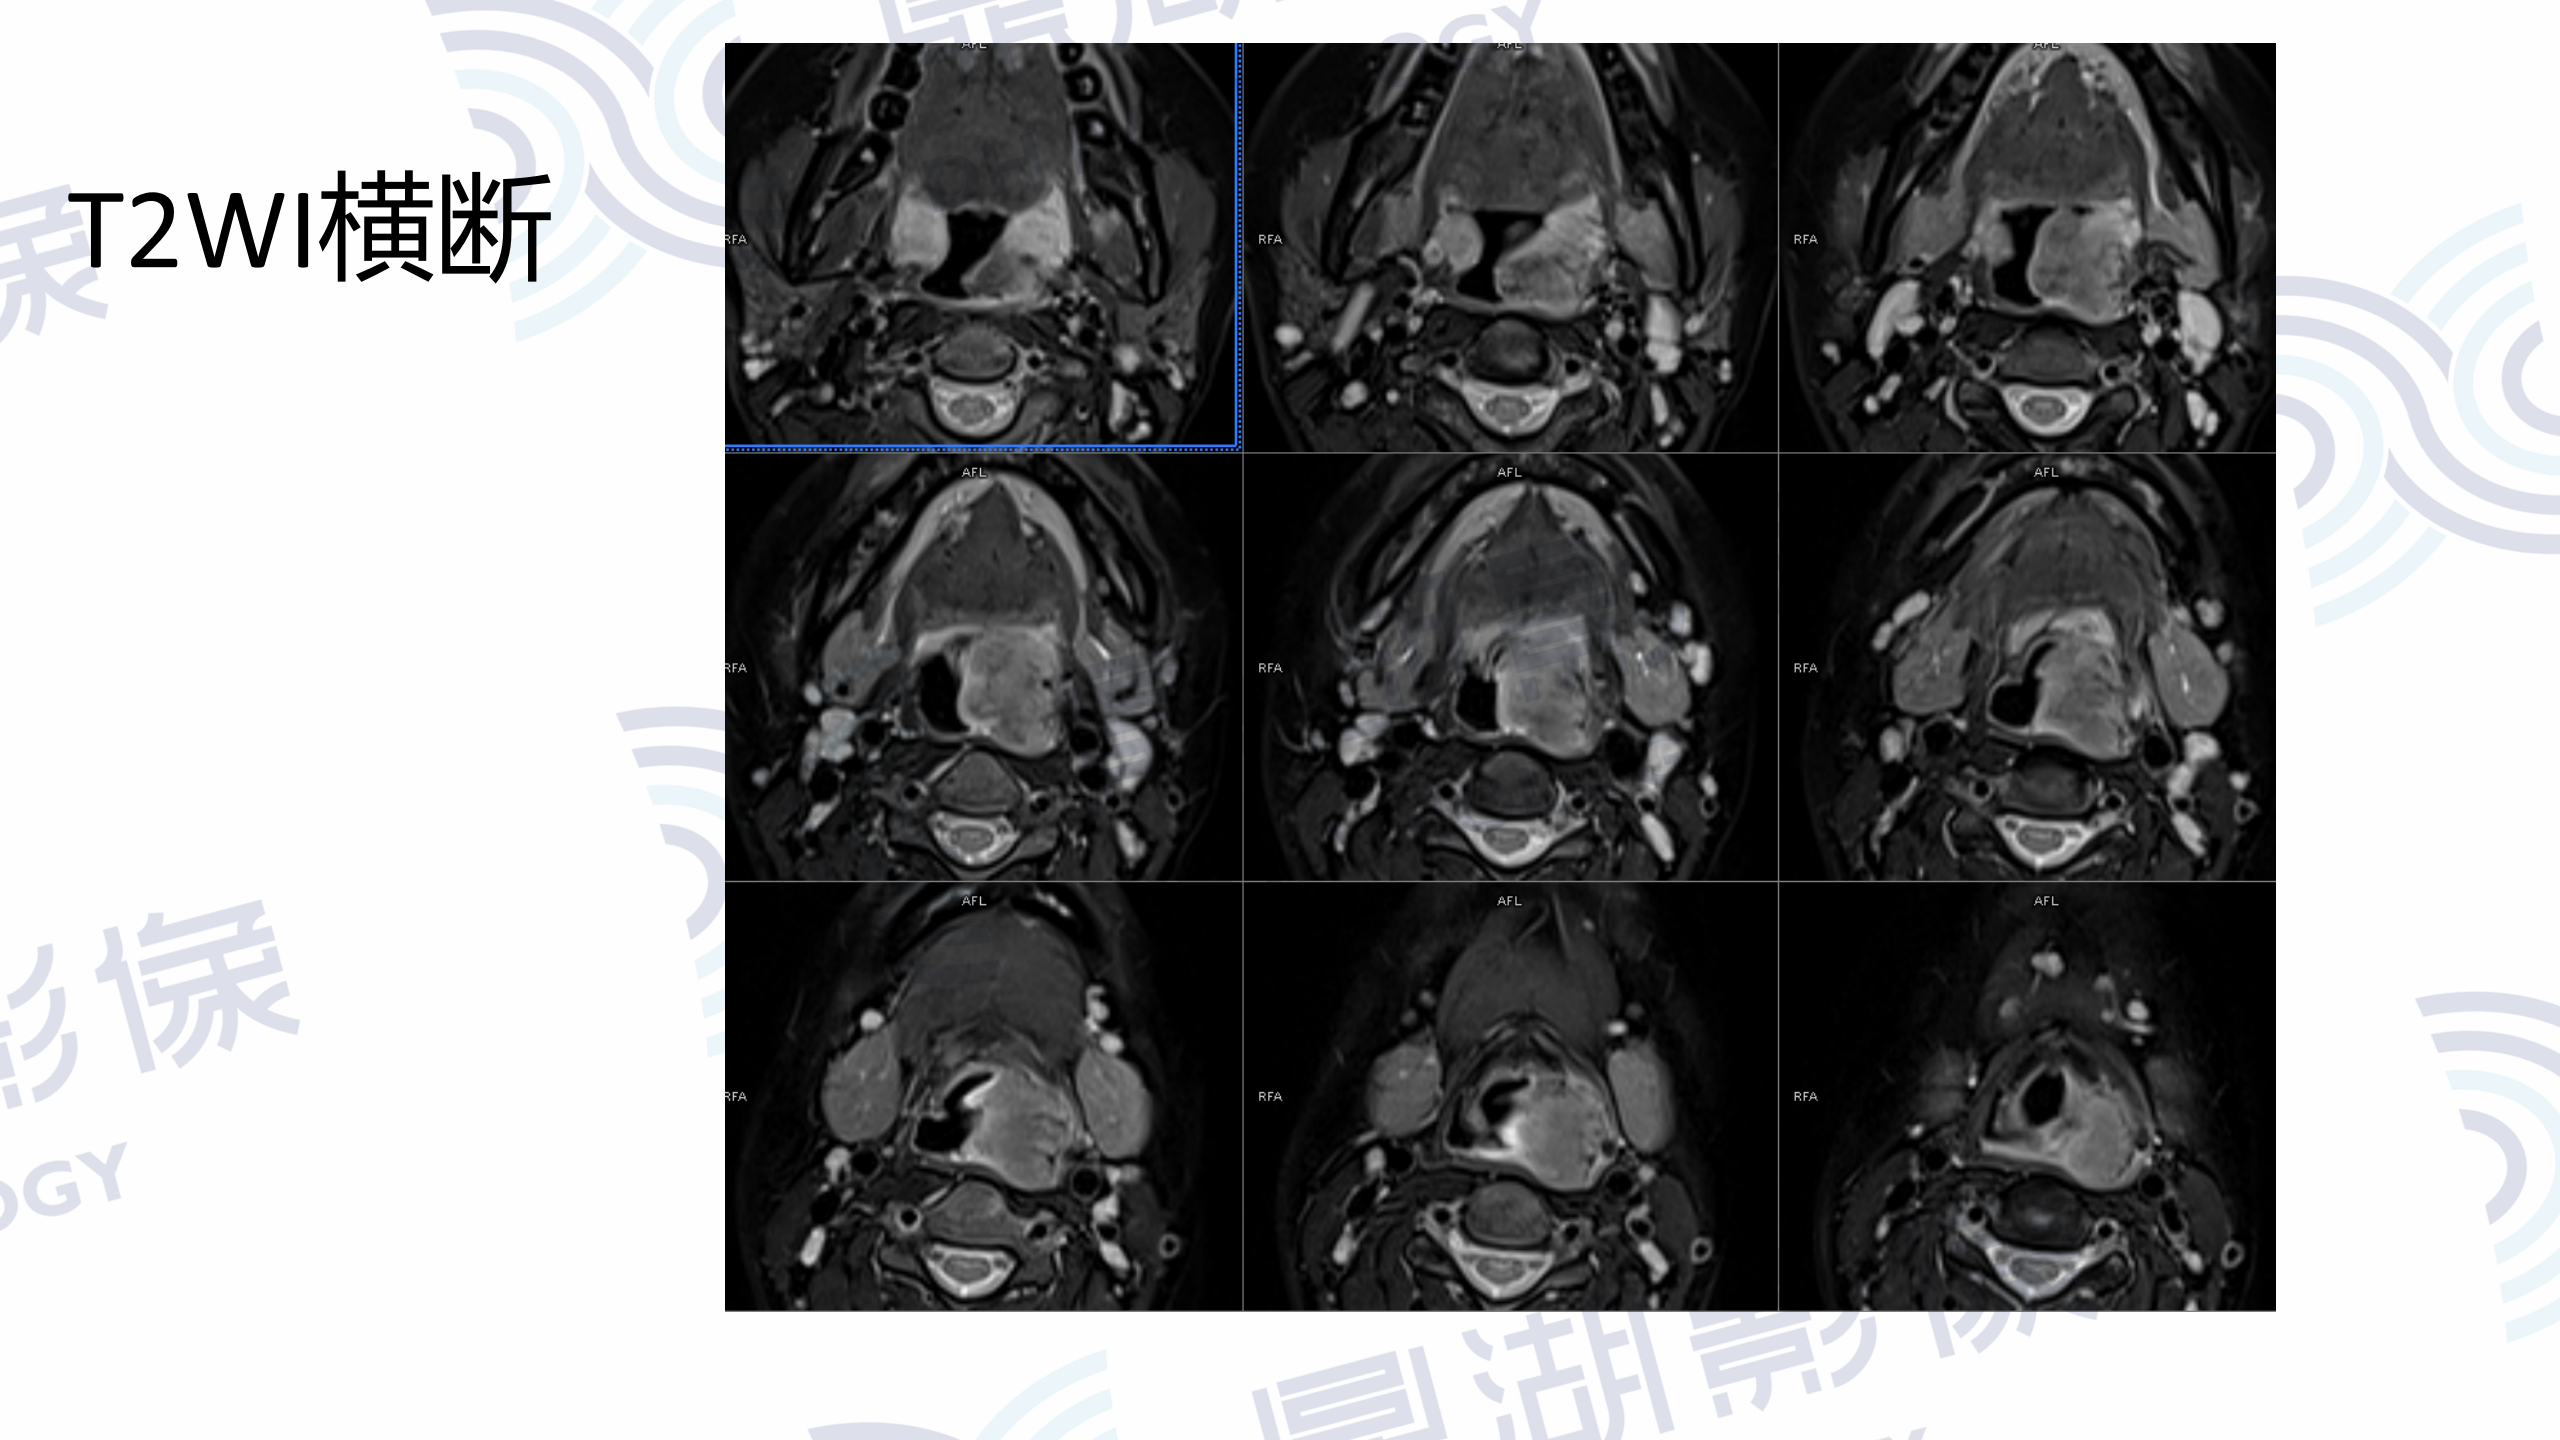

MR增强检查提示:口咽左侧壁至左侧声门上不规则软组织肿块,病灶突入咽腔,信号均匀,T1WI呈等信号,T2W呈稍高信号,DWI呈高信号,增强扫描呈轻度均匀强化,左侧杓状会厌皱襞水肿,左侧梨状窝消失。

口咽部活检病理为淋巴组织增生,IgG4浆细胞浸润阳性。